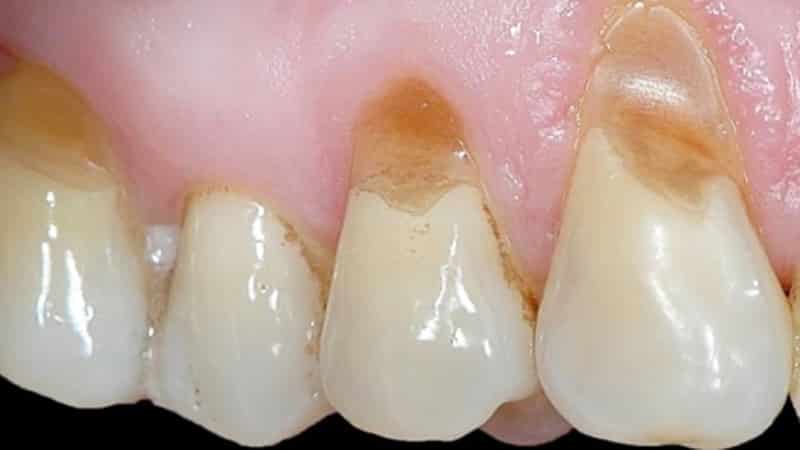

После второй стадии заболевания (глубина щели около 0,1 мм) наступает третья, когда дефект увеличивается до значительных размеров — 3,5 мм и более. В этот период шейка зуба становится очень чувствительной к раздражителям, пациенты испытывают дискомфорт при приеме пищи и периодическую резкую боль в этой области. Визуально эмаль выглядит неэстетично, ее оттенок может частично изменяться. Также процесс чистки зубов становится неприятным.

На следующей стадии происходит увеличение уступов до 0,5 см, при этом поражение затрагивает и мягкие ткани зуба (дентин). В некоторых случаях патология может распространиться на полость пульпы, что без своевременного лечения может привести к отколу коронковой части зуба. Однако даже в таких ситуациях заместительный дентин может предотвратить вскрытие камеры пульпы, что оставляет возможность для реставрации зуба.

Третья и четвертая стадии заболевания проявляются образованием глубоких трещин и щелей в эмали, которые могут затрагивать мягкие ткани дентина и даже пульпу зуба. В таких случаях простое «заделывание» трещин не принесет результата, так как повреждение будет продолжать углубляться внутри зуба.